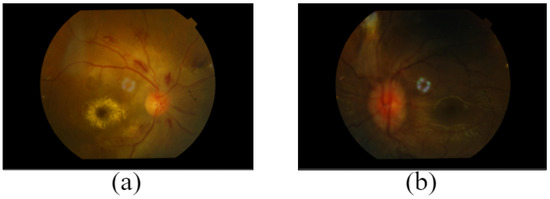

3.2. Data Acquisition

3.2.2. Quality of Image

- Eight-megapixel, high-quality images were produced by the integrated digital CCD camera. The angle of view was 45°.

- Fundus camera type: non-Mydriatic

- Auto-focus, auto-exposure, and auto-shoot are vital camera features.

- FF 450plus Fundus Camera and VISUPAC Digital Imaging System are seamlessly integrated for exceptional image quality, operation, and diagnostic adaptability.

- Through reciprocal calibration, the VISUPAC system and the FF 450plus Fundus Camera continuously deliver a distinct level of precision.

- For the fine detail of the macula and optic nerve, the Zeiss FF450 plus Fundus Camera offers three field angles: 50°, 30°, and the smaller 20° field.